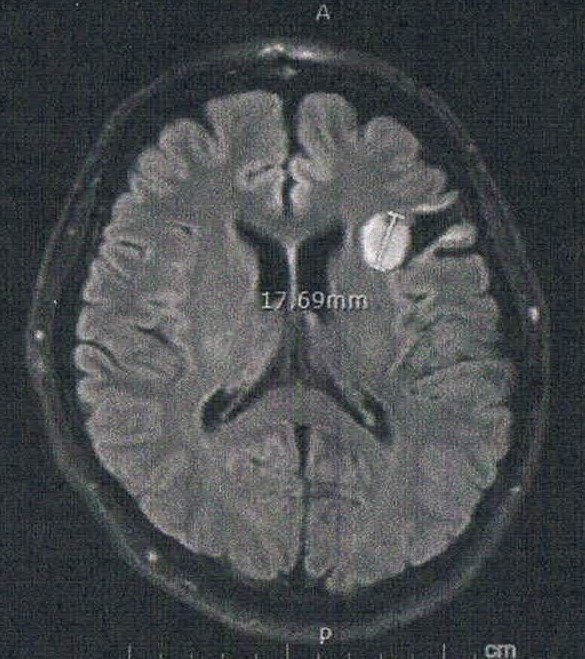

- びまん性星細胞腫グレード2(悪性転化しやすい腫瘍)

- 初めて前後方向に断面を見た気がするが、2年前の画像と比べると上方向に顕著に大きくなっている。

- 造影剤の有無でも見え方が違うのかもしれないが、上下方向は明らかに大きくなっている。玉子で例えると、直径は変わらないが上下が大きくなっている。